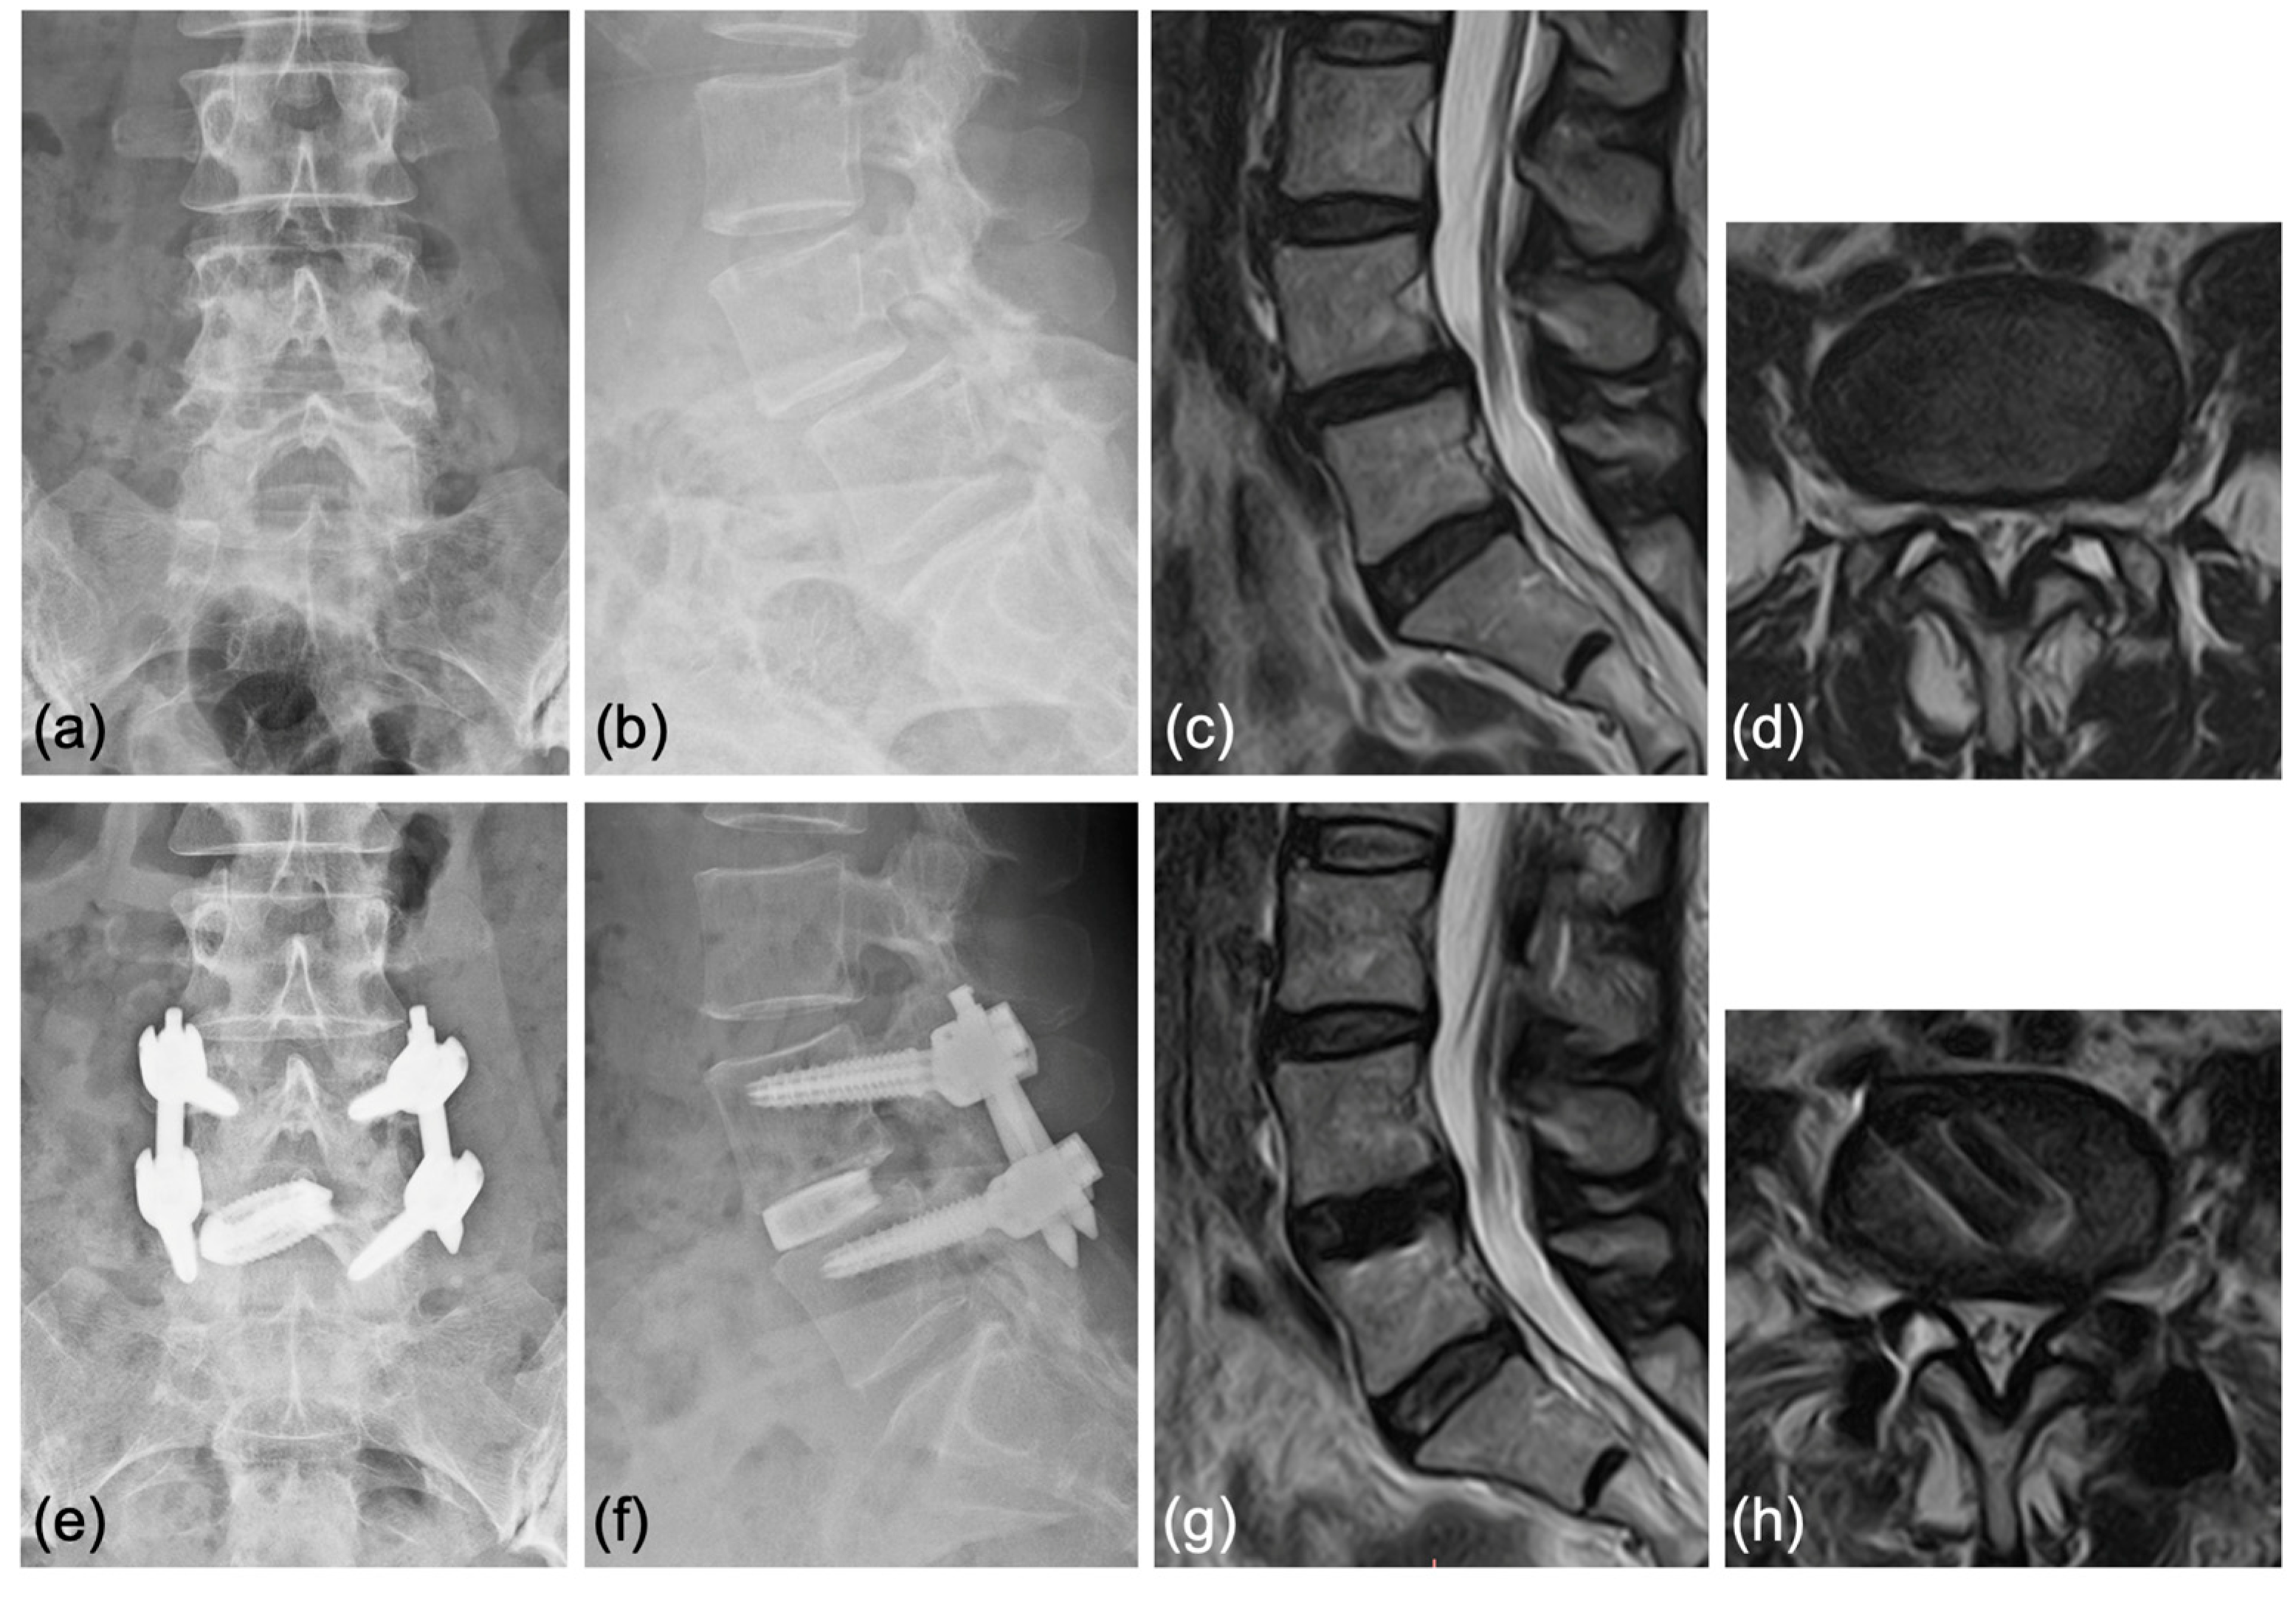

Figure 8.

Bony fusion through the titanium cage was confirmed by (a,b) anterior and posterior flexed lateral X-rays and (c,d) sagittal and coronal CT scans.